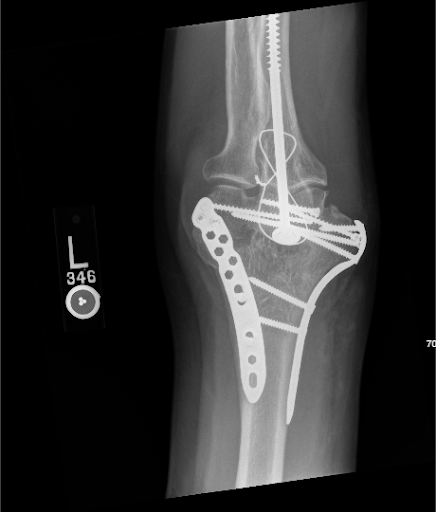

Medial plakanın çıkarılması her zaman gerekli olmayabilir; Bununla birlikte, bu durumda medial plakanın oldukça belirgin olduğunu hissettik, bu nedenle iyileşmiş bir kırık bağlamında çıkarılması hastanın bazı semptomlarını hafifletmeye yardımcı olacaktır. Ameliyat öncesi röntgenler dahildir: Transpoze sinirin etrafında adipofasiyal bir manşon oluşturulmasının, hasta üst ekstremiteyi hareket ettirirken sinirin kolayca kaymasına yardımcı olduğuna ve yara izi ve fibrozdan kaynaklanan tekrarlayan sinir sıkışmasını önlediğine inanıyoruz. Teknik, kısaca, burada bu şekilde açıklanmaktadır. Medial epikondil üzerinden posteromedial bir insizyon yapılır ve proksimal olarak 8-10 cm ve distal olarak 4-5 cm uzatılır. Ulnar sinir, dikkatli künt diseksiyondan sonra proksimal olarak, medial intermüsküler septumun hemen arkasında tanımlanır. Daha sonra, epinöryumun vasküler beslemesini sağlam tutmaya özen gösterilerek antegrad bir şekilde daha da diseke edilir. Sinir mobilize edildikten ve anterior olarak transpoze edildikten sonra, dikkat adipofasiyal flebe çevrilir. Vasküler besleme yerinde olan flep, arkadan öne dikkatlice sarılır ve tüm sinir uzunluğunu çevreleyen bir tünel oluşturmak için dikilir. Son olarak, sinirin bükülmediğinden emin olmak için dirseğin açılması yapılır. Bu teknik, bu gibi durumlarda özel uygulama ile literatürde iyi tanımlanmıştır. 12–14

Şekil 1. Ameliyat öncesi plakaların konumunu gösteren Sol dirsek röntgeninin AP görünümü.